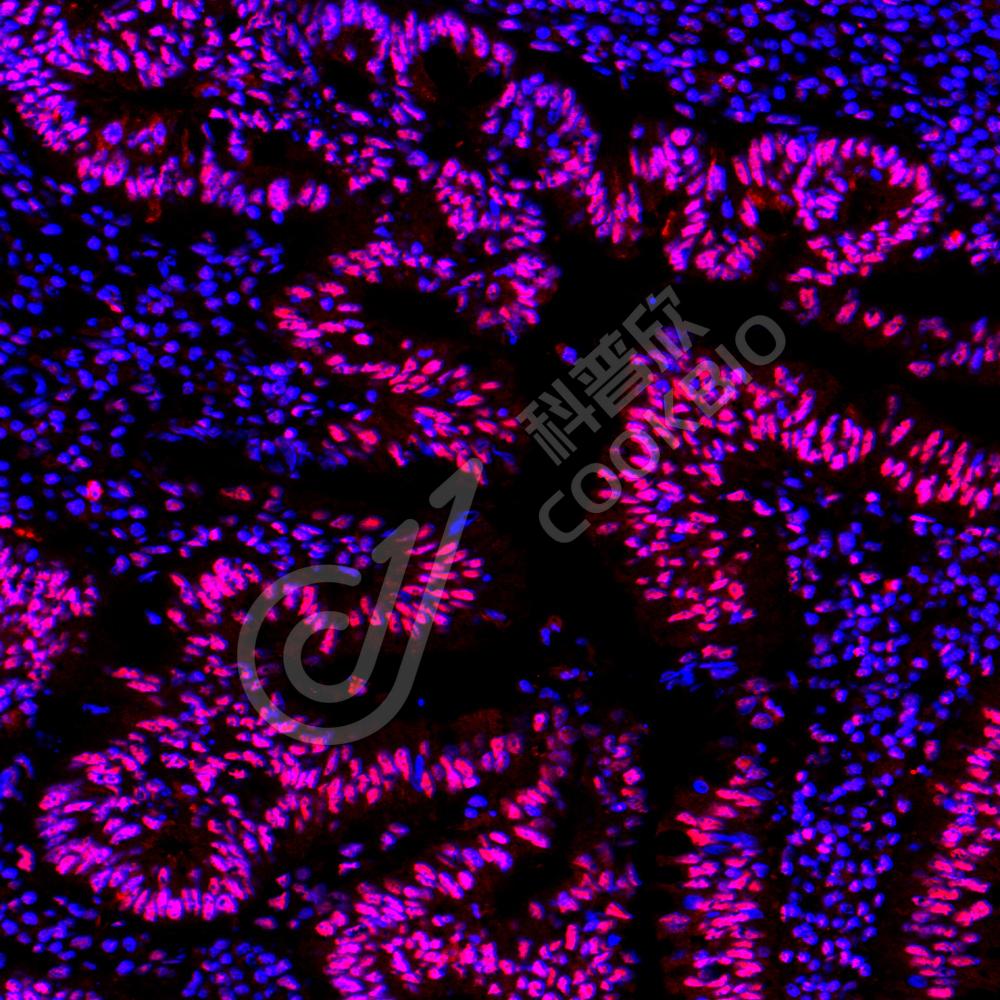

IHC检测Phospho-GSK3 Beta(S9)蛋白(货号 K5450150).

样品: 人肝癌, 4%多聚甲醛 (货号KSG1101) 固定12-24小时.

抗原修复: 柠檬酸抗原修复液(干粉, pH 6.0) (KSG1201), 高压锅均匀喷气计时2分钟.

—抗: 1: 500稀释, 4℃ 孵育过夜.

二抗: S-vision免疫组化多聚二抗(山羊抗兔),即用型 (货号KB3906), 室温孵育20分钟.